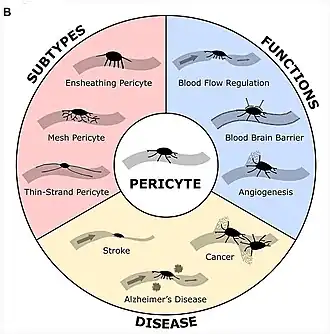

Pericyten (vroeger Rouget-cellen genoemd)[1] zijn multifunctionele cellen van de microcirculatie, die rondom de endotheelcellen van de haarvaten zitten.[2] Ze hebben primaire uitlopers die zich in de lengterichting langs de haarvatwand uitstrekken en secundaire laterale uitlopers die zich rondom het haarvat uitstrekken. Het cytoplasma van pericyten bevat microtubuli die zich langs de as van de primaire uitsteeksels uitstrekken. Ze werden voor het eerst geïdentificeerd in de jaren 1870, maar er werd in de daaropvolgende eeuw weinig aandacht aan besteed.[3] De naam pericyt werd door Zimmerman in 1923 aan de cel gegeven.[4] Pericyten zijn ingebed in het basaalmembraan van haarvaten, waar ze communiceren met endotheelcellen door middel van zowel direct fysiek contact als paracriene celsignalering.[5] De morfologie, distributie, dichtheid en moleculaire vingerafdrukken van pericyten variëren tussen organen en bloedvaten.[6][7] Pericyten helpen bij het handhaven van homeostatische en hemostatische functies in de hersenen, dat een van de organen is die wordt gekenmerkt door een hogere pericytbedekking. Ze ondersteunen ook de bloed-hersenbarrière.[8] Deze cellen zijn ook een belangrijk onderdeel van het neurovasculair systeem, die endotheelcellen, astrocyten en zenuwcellen omvat.[9][10] Er wordt verondersteld dat pericyten de bloedstroom door de haarvaten reguleren.[11][12][13][14] In vitro verwijderden ze celresten door fagocytose.[15] Pericyten stabiliseren en bewaken de rijping van endotheelcellen door middel van directe communicatie tussen het celmembraan en via paracriene signalering.[16] Een tekort aan pericyten in het centraal zenuwstelsel kan leiden tot een verhoogde doorlaatbaarheid van de bloed-hersenbarrière.[8]

De interstitiële druk waaraan pericyten worden blootgesteld, zal naar verwachting voor elk subtype verschillen vanwege de verschillen in lokalisatie; de druk wordt geschat op ongeveer 50 mmHg voor ePC's, ongeveer 30 mmHg voor tsPC's en ongeveer 15 mmHg voor sPC's. ePC's zijn pericyten rondom pre-haarvaten, tsPC's zijn dunstrengige pericyten op haarvaten en sPC's zijn stervormige pericyten op post-haarvaten.[38]

Vanwege hun cruciale rol bij het handhaven en reguleren van de structuur van endotheelcellen en de bloedstroom, worden afwijkingen in de pericytfunctie gezien bij veel pathologieën. Ze kunnen ofwel in overmaat aanwezig zijn, wat leidt tot ziekten zoals hypertensie en tumorvorming, of in deficiëntie, wat leidt tot neurodegeneratieve ziekten, zoals de ziekte van Alzheimer, de ziekte van Parkinson en ALS.